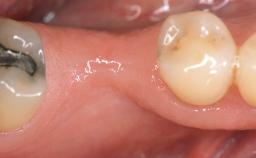

A 30-year-old woman was referred by her general dentist for evaluation of an esthetic complication related to previous implant treatment for congenitally missing maxillary lateral incisors. The patient’s chief complaint was the inadequate esthetic appearance of her smile. The case demonstrates the use of a combined approach to achieve optimal results. Two different flap designs - a tunnel technique and a coronally advanced flap - are employed based on the surgical objectives for the affected site.

Soft Tissue Grafting Yes

Soft Tissue Anatomy Intact Defective

Soft Tissue Contour and Volume Slightly compromised